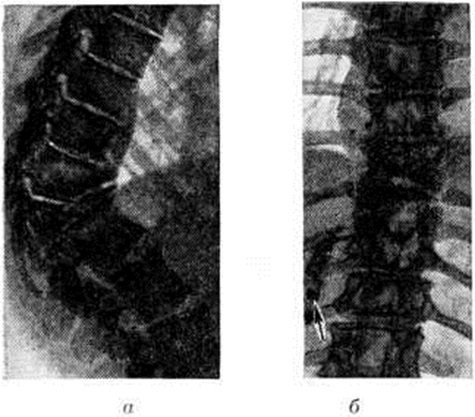

Рис. 5.

Рентгенограммы части грудного и поясничного отделов позвоночника больного туберкулёзным спондилитом: а — боковая проекция; б — прямая проекция; 1 — костная каверна в телах X и XI грудных позвонков; 2 — тень натечного абсцесса.

Во многих случаях при туберкулёзном Спондилит натечные абсцессы могут быть диагностированы рентгенологически. В шейном отделе позвоночника абсцесс распознается по дугообразному выпячиванию задней стенки трахеи и глотки. В грудном отделе тень абсцесса на фоне лёгочных полей довольно отчётливо дифференцируется и имеет форму веретена, луковицы и так далее Очертания абсцесса гладкие и чёткие (рисунок 5). Для уточнения объёма и распространённости абсцесса применяют абсцессографию (рентгенологические исследование после заполнения опорожненной полости абсцесса контрастным веществом), а при наличии свища — фистулографию (смотри полный свод знаний). В поясничном отделе абсцессы диагностируются по косвенным признакам — выпячиванию наружного края большой поясничной мышцы.

По мере затихания и последующей стабилизации туберкулёзного процесса натечный абсцесс может рассосаться или обызвествиться. Обызвествленные участки имеют вид мелких или крупных конгломератов (рисунок 6). Рентгенологические признаками затихания туберкулёзного Спондилит являются: уменьшение размеров абсцесса, увеличение его плотности или обызвествление; стабильность рентгенологическое признаков без появления новых деструктивных изменений, четкая отграниченность каверн; окостенение фиброзных колец и продольных связок позвоночника в виде скобок и краевых разрастаний; костное спаяние (анкилозирование) дуг и суставных отростков позвонков.